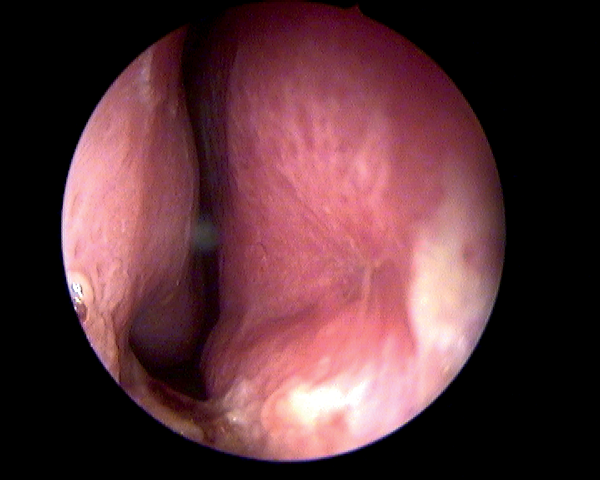

Only after completing the roof and floor flaps, the mucosal perforation itself is separated using sharp dissection and its edges refreshed (Figures 3a and b).

Figures 3a (top) and 3b (above): Mucosal advancement for closure.